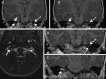

Methods: High resolution MRI was performed in children genetically proven to have NF2. The superior vestibular nerve (SVN) and inferior vestibular nerve (IVN) were visualised along their course with points of tumour origin calculated as a percentage relative to the length of the nerve.

Results: Out of 41 patients assessed, 7 patients had no identifiable eighth cranial nerve disease. In 16 patients there was complete filling of the internal auditory meatus by a tumour mass such that its specific neural origin could not be determined. In the remaining 18 cases, 86 discrete separate foci of tumour origin on the SVN or IVN could be identified including 23 tumours on the right SVN, 26 tumours on the right IVN, 18 tumours on the left SVN and 19 tumours on the left IVN.